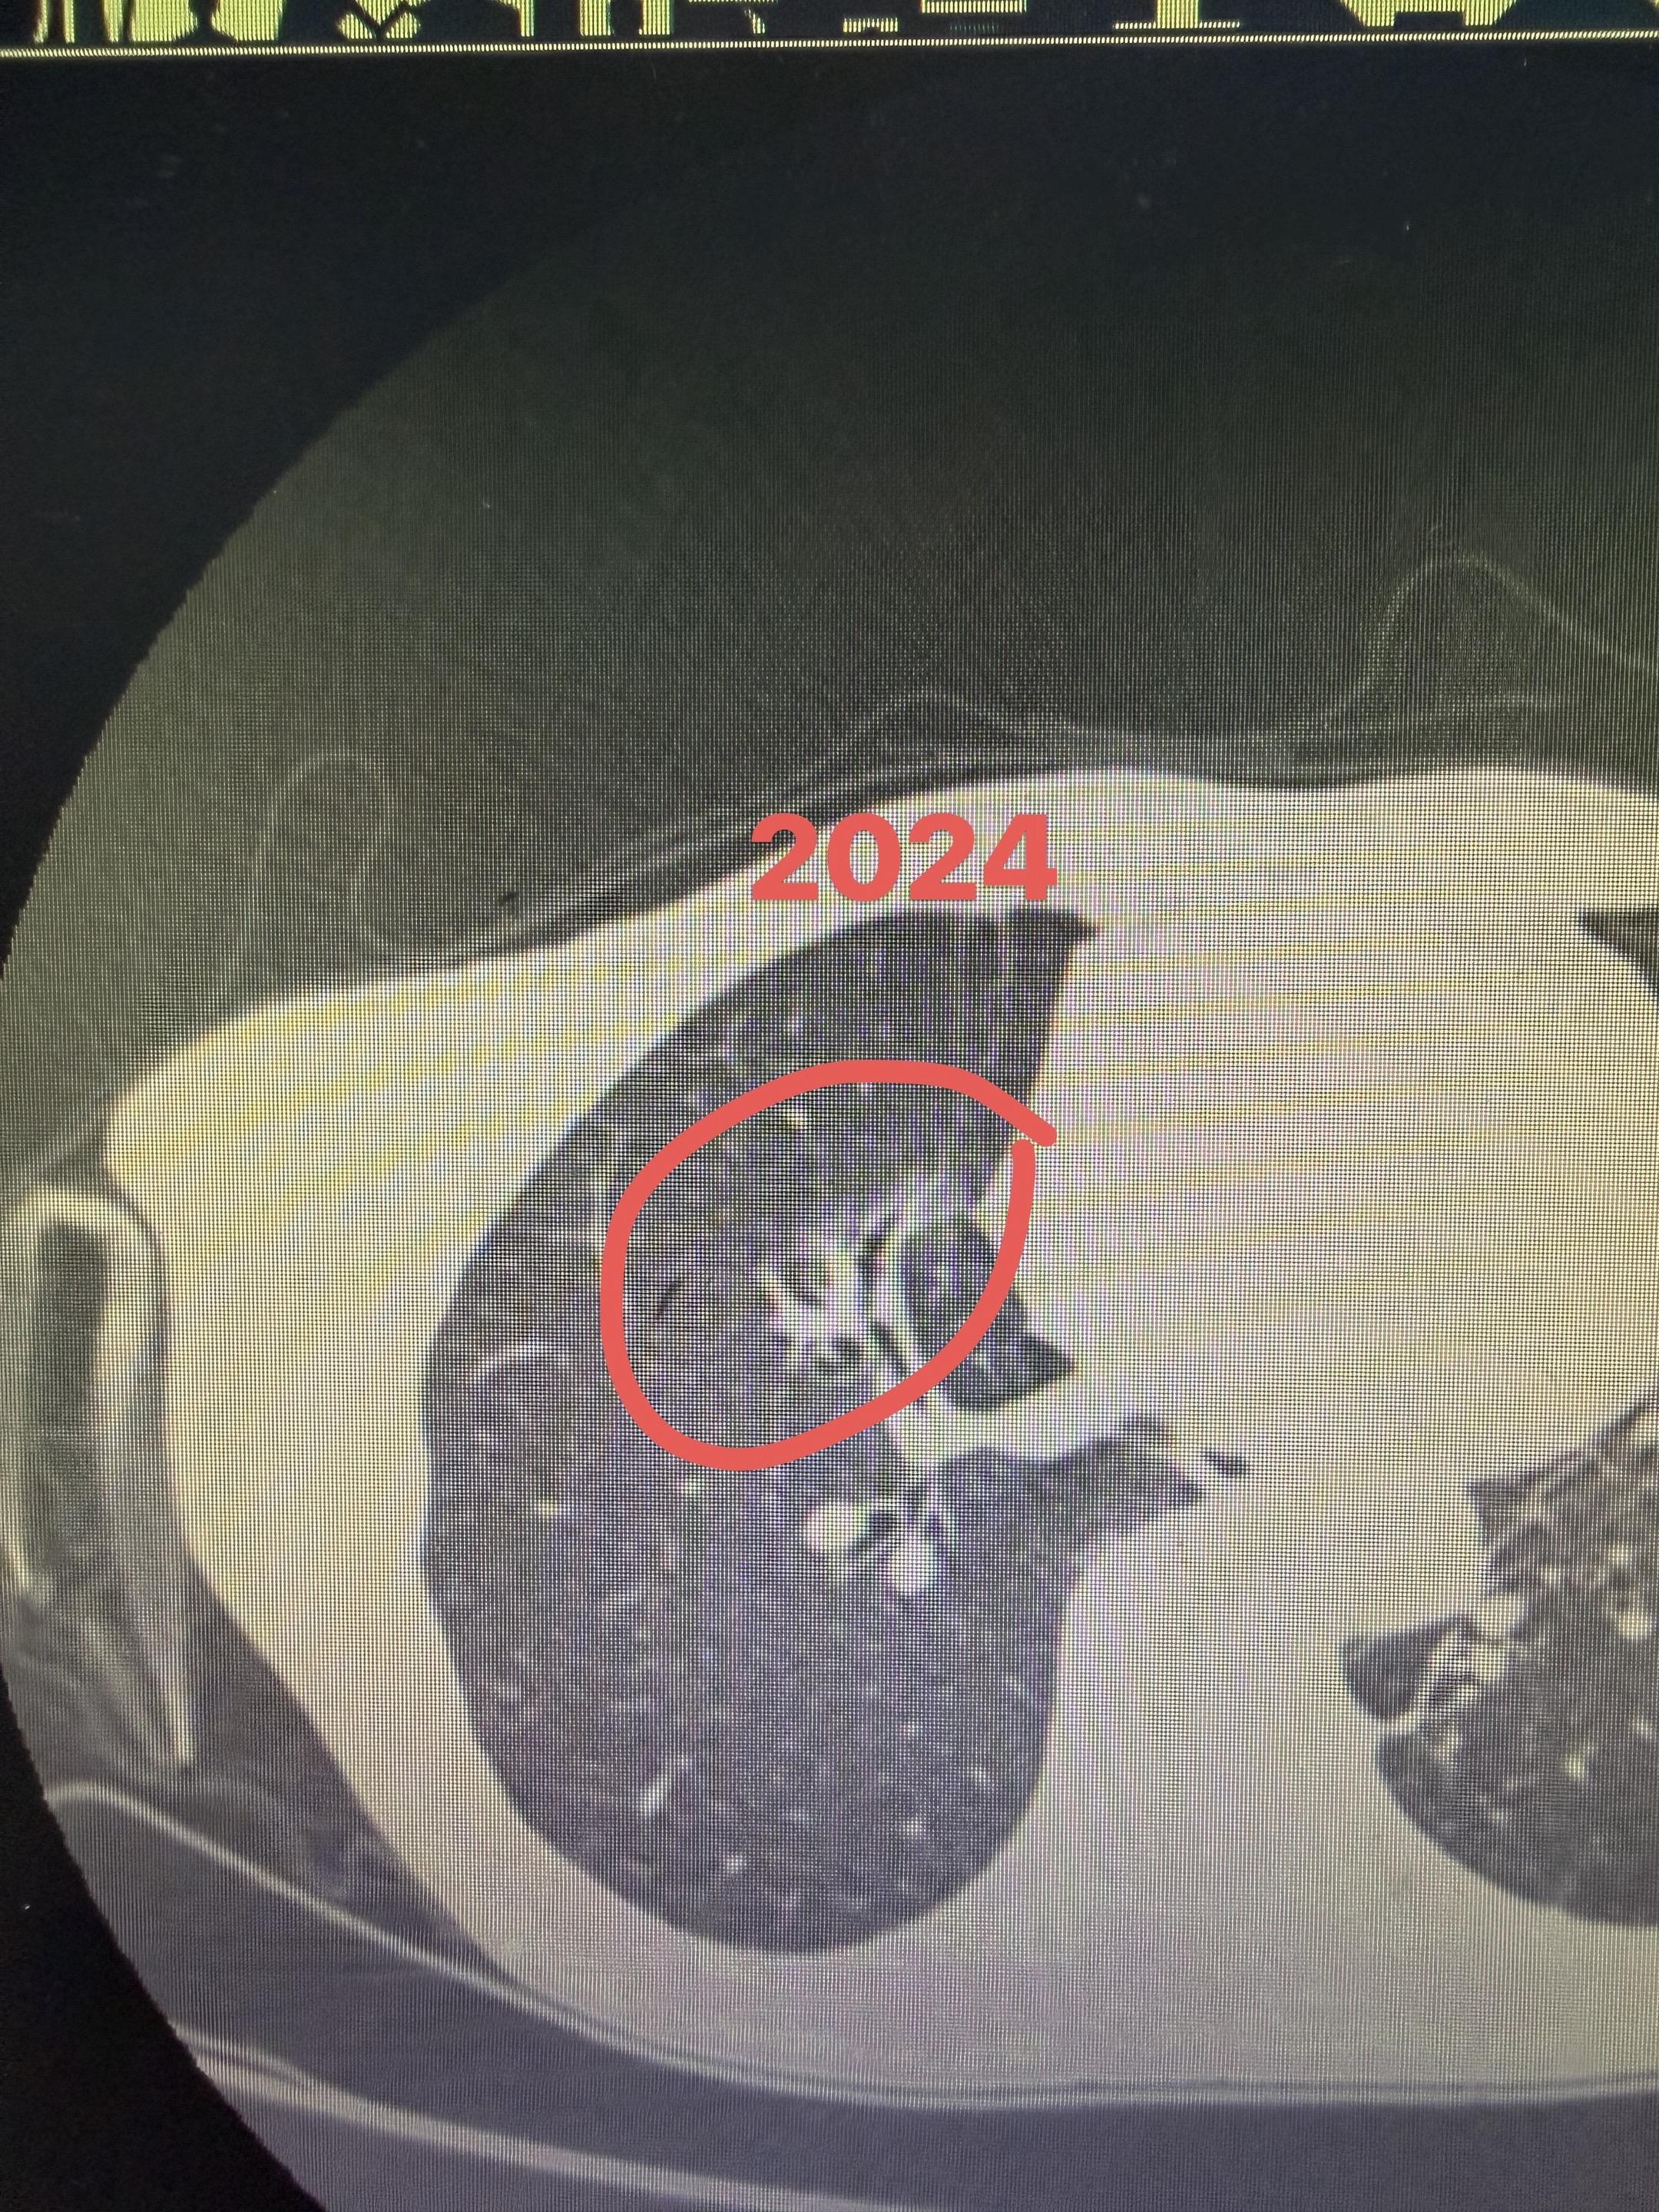

靶向药可以让部分磨玻璃缩小。的确,我们也观察到,靶向药可以让部分磨玻璃缩小,但是哪些会缩小,哪些不会缩小,其实也是有道道的[调皮]下图是我们的病人,双肺多发浸润性腺癌,目前已经术后7年。在随访的过程中,又一个磨玻璃冒头,被我们用靶向药打下去[微笑]